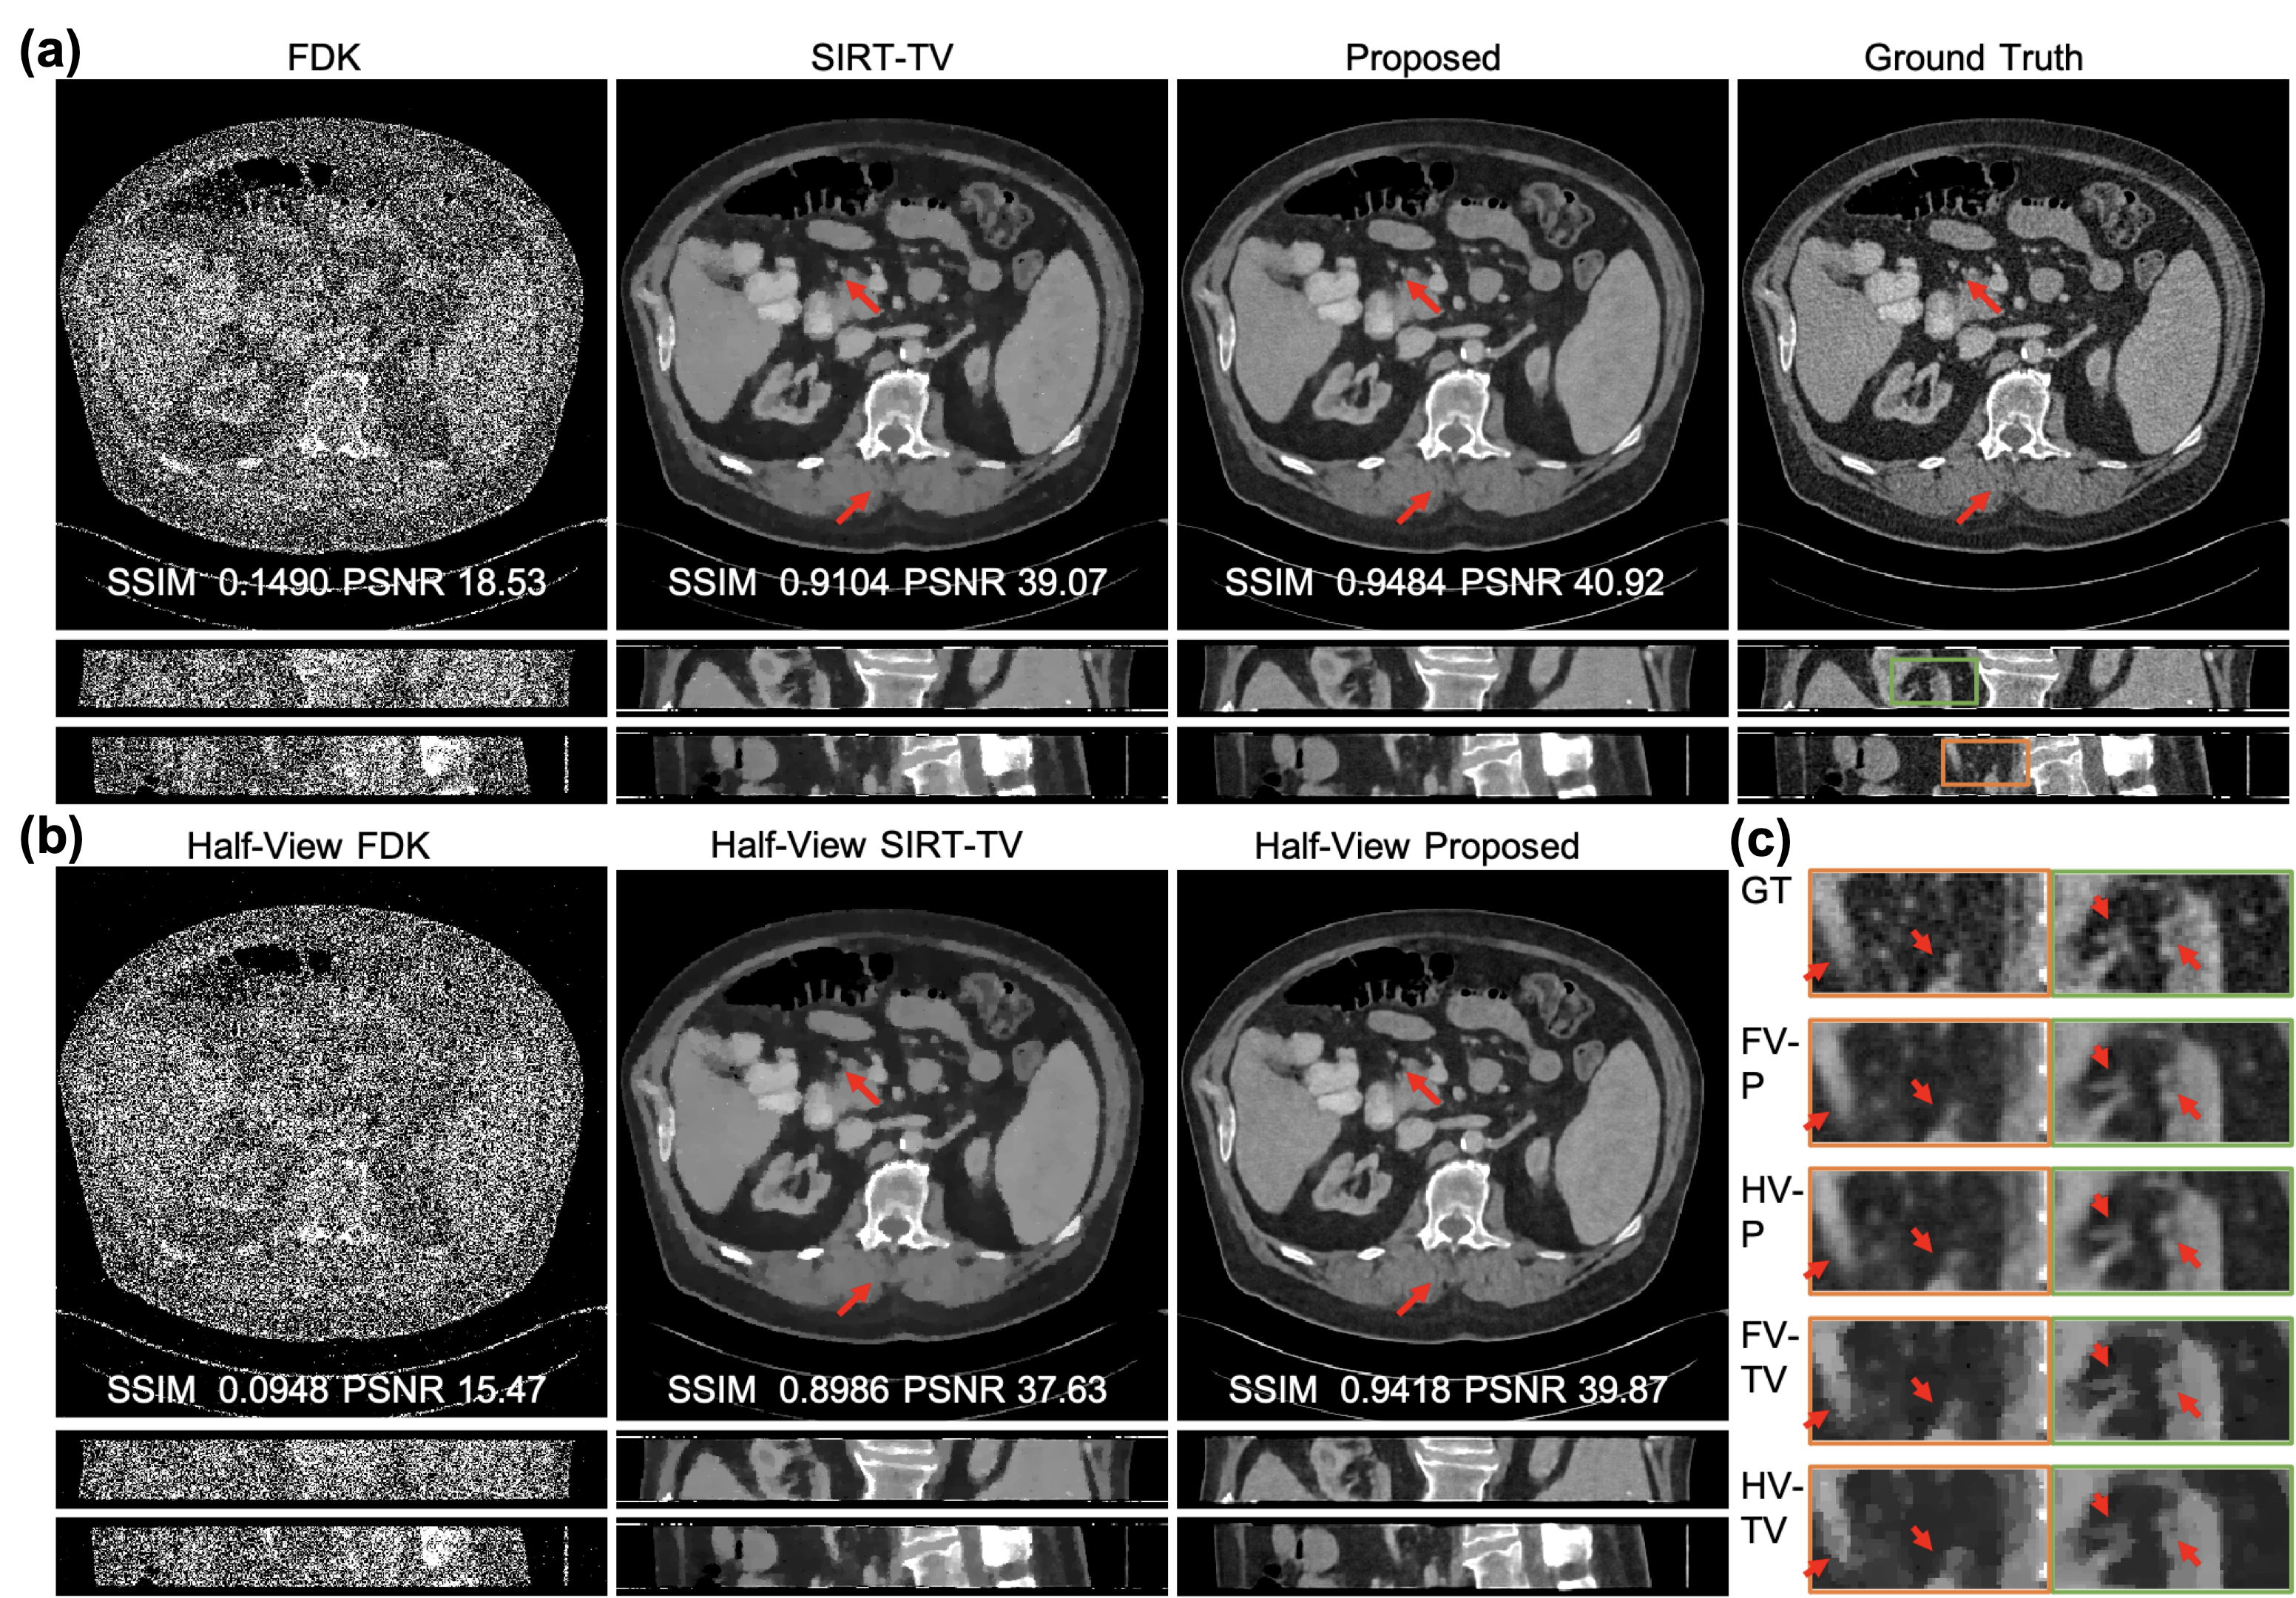

Representative full-view and half-view reconstructions are shown in Fig. 5. The fine details indicated by the red arrows are successfully restored with our methods for both full-view and half-view cases while missing structures or distortions are observed with the SIRT-TV particularly in the half-view scenario. Additionally, unnatural waxiness is also observed in the zoom-in regions of SIRT-TV results. Moreover, our half-view reconstruction scores are even better than the full-view reconstruction with the conventional method in terms of structural similarity index metric (SSIM) and peak signal-to-noise ratio (PSNR) metric, demonstrating the superiority of our method. More importantly, our method demonstrates impressive stable performance despite significant acquisition condition change from full-view to half-view (<1.0%absentpercent1.0<1.0\%< 1.0 % loss in SSIM and <4.0%absentpercent4.0<4.0\%< 4.0 % loss in PSNR), which is even more robust than the classic SIRT-TV.

Refer to caption

Figure 5: Representative images reconstructed using competing methods on simulated data. (a) The full-view reconstructions with FDK, SIRT-TV, and our method displayed against the ground truth, with exemplary axial, coronal, and sagittal views included from top to bottom; (b) the reconstructions from halved views; and (c) magnified regions from the coronal and sagittal views as indicated by the green and orange boxes respectively and displayed in the descent order of image sharpness and structural fidelity: ground truth (GT), our full-view and half-view reconstructions (FV-P, HV-P), and full-view and half-view reconstructions with SIRT-TV (FV-TV, HV-TV) from top to bottom. The display window is W/L:400/50 HU. The red arrows indicate the structural details are easy to recover for our methods but challenging for SIRT-TV.